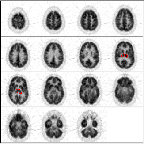

This is a normal PET scan. Abnormal PET scans will be compared with it in this tutorial about image quality control. The checklist on the right will be completed as we work through image quality control issues relating to neurological scan evaluation. This scan depicts fifteen planes (imaged simultaneously). The top of the brain begins in the upper left corner. Moving from left to right through each row, the final image is from the bottom of the brain.